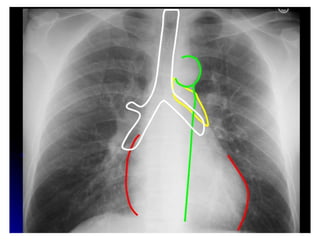

PA VIEW                            AP VIEW

• Chin up , shoulders rotated    • Taken in cases when patient

forward, taken in full           is too ill to stand

inspiration

• With plate in front of chest   • Film is placed behind the

and back to the X-ray            back and x-ray exposure

machine                          from front .

• Scapula away from the          • Scapula closer to the lung

upper lung fields                fields

• Clavicles less apically        • Clavicles less apically

displaced                        displaced

• Vertebral neural arches        • Vertebral disc spaces seen

seen                             better

• Relative cardiomegaly